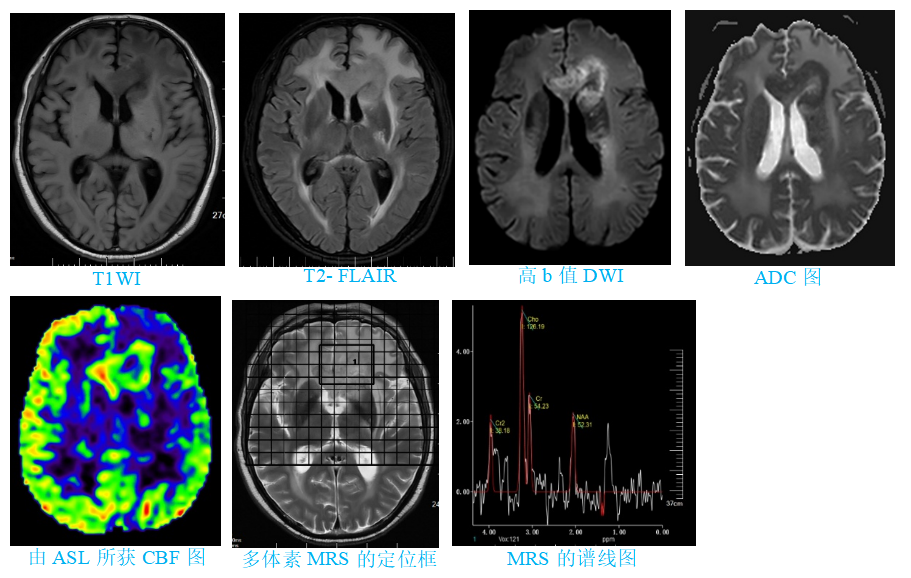

ASL正在成为医学影像科医生手中一项强大的工具,能帮助我们更好地洞察大脑的健康状况,结合其它相关影像学检查更可提高诊断效能。此前,一位患者做常规MRI平扫和DWI检查时,发现左额叶有病变,还累及到左侧基底节区和胼胝体。但该患者肾功能不好,不宜做需要打对比剂的常规磁共振增强检查。为了确定病变到底是什么,遂行ASL和MRS检查,结果清楚地看到病变区域的血流和代谢异常,提示病变为肿瘤,为后续治疗方案的确定提供了可靠依据。